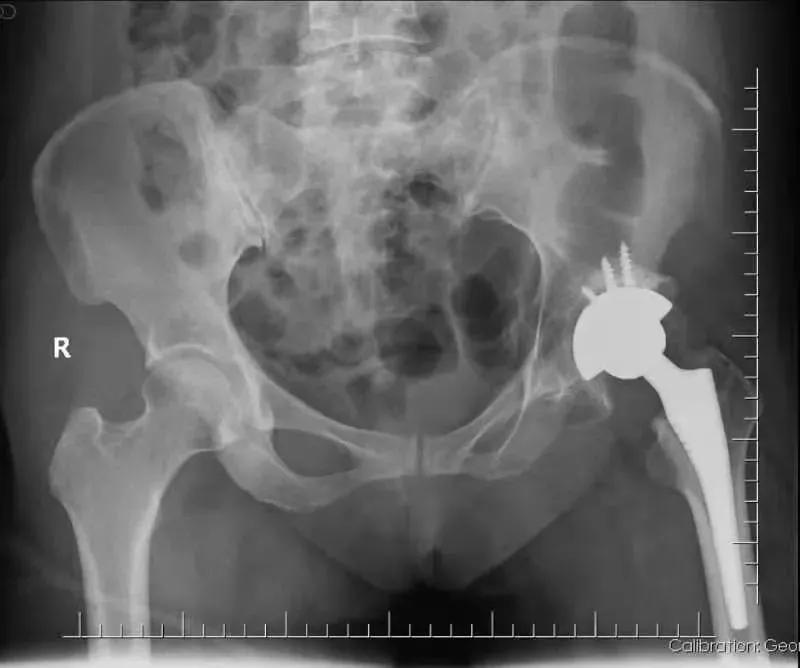

骨一科刘学东主任、黄思聪副主任医师组成手术团队共同为张女士完成了左侧全髋关节置换术、髋关节滑膜切除和髋关节松解术。

手术十分顺利!术后,张女士在助行器的帮助下,缓慢行走,原本疼痛的髋关节,也终于不再痛了。 张女士对手术效果十分满意。